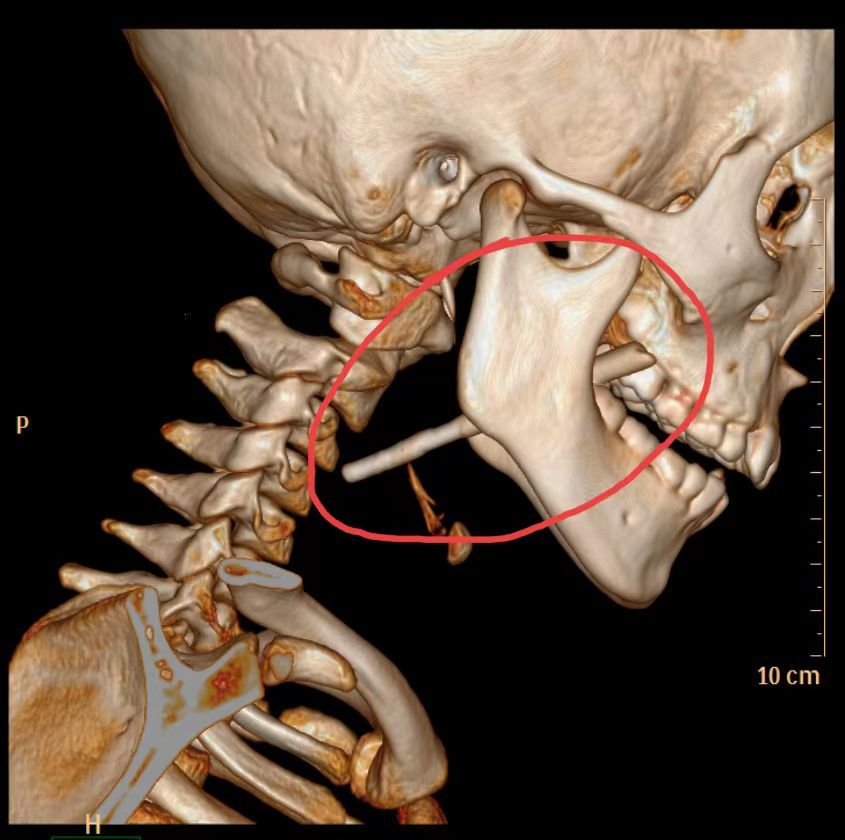

为了确保手术中的安全,医师给阳阳做了CT检查,发现一条状(筷子样)致密影经右侧下颌骨后方达左侧咽喉部后方(咽后壁),左侧咽后部局部软组织有肿胀,咽后壁及气管/食管周围软组织内可见多发气体密度影、下方达上纵隔(主动脉弓上方水平)。耳鼻咽喉头颈外科医师在急诊全麻及气管插管下为孩子实施了咽部异物取出术+咽部清创术,术中取出筷子残端,长约9.3cm。